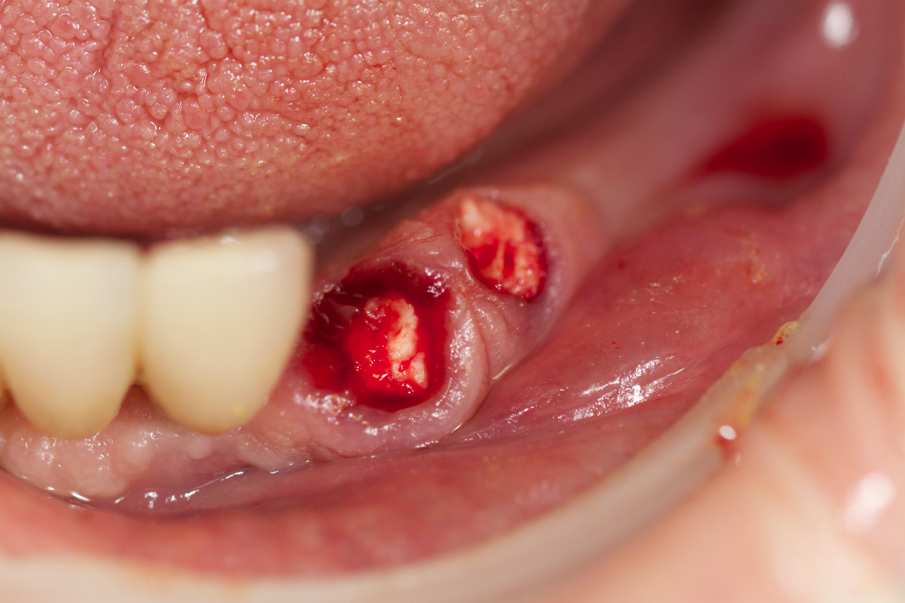

Fig.12 - Gli elementi 3.3 e 3.4 devono essere estratti.

Fig. 13 - Avulsione di 3.3 e 3.4.

Fig. 14 - Spugne emostatiche (Hemocollagene, Septodont) sono state inserite nei siti di estrazione.